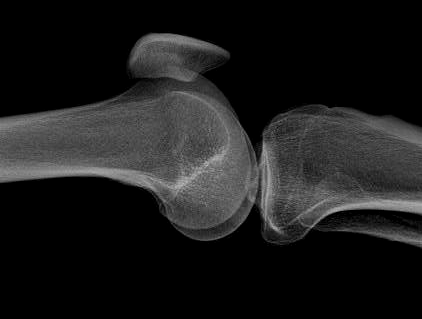

Several results from our method are shown in Fig. 7. The left column is the original input image. The right two columns are the soft tissue and bone image, respectively. It can be told that the soft tissue image is smooth as we assumed. Meanwhile, the bone image has better image contrast as desired. Moreover, our method can reach real-time performance on these X-ray images. The running time of our method on these images is reported in Table I.

Refer to caption

(a) original

(b) soft tissue

(c) bone (α=1.34𝛼1.34\alpha=1.34)

(d) original

(e) soft tissue

(f) bone (α=1.08𝛼1.08\alpha=1.08)

(g) original

(h) soft tissue

(i) bone (α=1.42𝛼1.42\alpha=1.42)

(j) original

(k) soft tissue

(l) bone (α=1.49𝛼1.49\alpha=1.49)

Figure 7: More results by our method. Input X-ray images (left), our estimated soft tissue (middle) and estimated bone image (right).